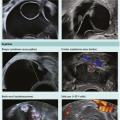

L’imagerie des lésions ovariennes repose sur le triptyque : échographie endovaginale avec Doppler, imagerie par résonance mag­nétique (IRM) et tomodensitométrie (TDM). Si l’échographie reste l’examen de première intention, en fonction de la question posée et du type de lésion ­découverte, la réalisation d’une IRM pelvienne ou d…